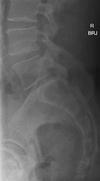

Radiographer X-ray Findings:

Findings

As requested, a spot lateral and a lateral view have been performed.

There appears to be a very minor anterolisthesis of L5 relative to S1 in the order of only 2-3mm and degenerative.

There is no other malalignment.

There is no fracture.

There is no destructive pathology.

There is good preservation of intervertebral disc heights.